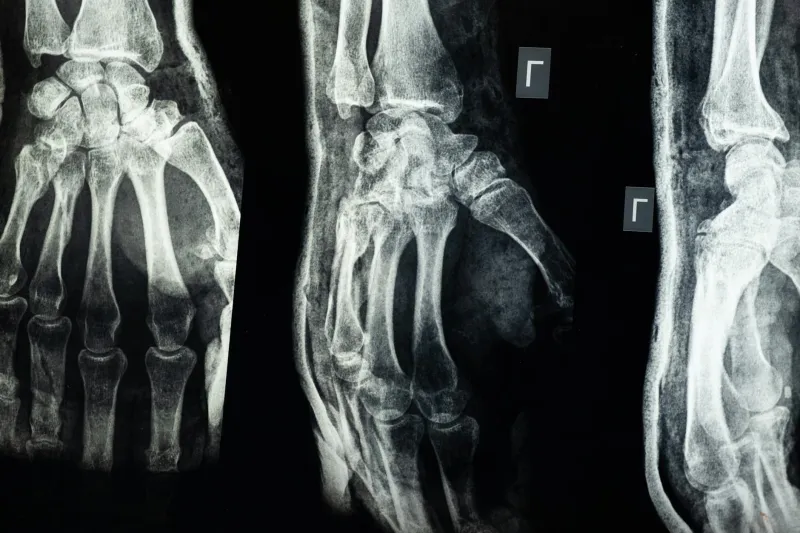

The real breakthrough came in the 1890s with the arrival of X-ray technology. For the first time in human history, doctors could see inside the body without cutting it open. Dr. Harvey Cushing at Johns Hopkins described the first X-ray images as "miraculous"—and they were. Suddenly, physicians could diagnose fractures accurately, see how bones were healing, and plan treatments with unprecedented precision.

Fast-forward to today, and the contrast is staggering. A compound fracture that would have meant certain amputation in 1870 is now routinely repaired with titanium plates and screws. Hip replacements—unimaginable a century ago—are performed 450,000 times annually in the United States. Patients walk the same day.

The statistics reveal just how dramatically things have changed. In 1900, the amputation rate for compound fractures exceeded 50%. Today, it's less than 2%. A century ago, the average hospital stay for a broken leg was 6-8 weeks. Now, many fracture repairs are outpatient procedures.